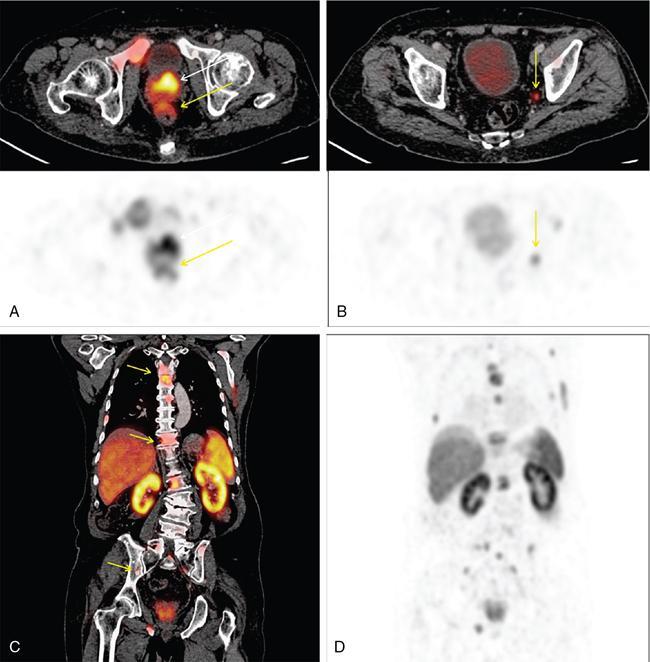

Karthik Ganesan, Disha Lokhandwala, Ujjwal Bhure, Jay Mehta Morphogenesis of the male genitourinary system is governed by the coherent interaction of three units, namely the Wolffian duct, urogenital sinus and foetal gonads. The Wolffian ducts are the embryonic precursors of the male internal genitalia, arising in the anterior intermediate mesoderm at 4 weeks of gestation. They elongate as a cord of cells that caudally extend to the urogenital sinus. Between 5 and 8 weeks of gestation, the urorectal septum divides the cloaca into a ventral compartment, which forms the urogenital sinus, and a dorsal compartment, which forms the rectum. The gonads form as epithelial thickenings on the ventromedial surface of the mesonephros and produce testosterone at 8 weeks of gestation, reaching a peak at 10–15 weeks. Under the effect of testosterone produced by the foetal testis, the prostate anlage forms at the tenth week of gestation. Precursor of the anlage begins with proliferation of solid epithelial buds from the epithelium of the urogenital septum into the adjoining mesenchyme in response to interaction of 5α-dihydrotestosterone with mesenchymal androgen receptors. As growth progresses, solid cords of epithelial cells are formed, growing into the mesenchyme in a specific three-dimensional arrangement (establishes the lobar divisions of the prostate gland). These solid cords develop a central lumen at birth and are lined by a layer of flat basal epithelium and a luminal layer of tall columnar secretory epithelium. Mesenchymal component forms the stroma, which has a large proportion of smooth muscle. Postnatally, the epithelial cords continue to arborize till puberty without any change in volume or glandular architecture. Although the foetal prostate has been described to have a histologically distinct peripheral zone (PZ) as early as 12 weeks of gestation, the mature zonal anatomy develops in concordance with the androgen surge at puberty. The most commonly utilized ultrasonographic technique for the evaluation of the prostate is via a suprapubic approach. The abdominal transducers used in this approach are relatively low frequency and while it offers the advantage of greater depth of penetration without intracavitary probe insertion; however, it does not depict the zonal anatomy and its chief application lies in volume estimation. Hence, transrectal ultrasonography (TRUS) completely outweighs the transabdominal approach in terms of depicting zonal anatomy, visualizing and localizing small lesions, demonstrating vascularity and performing biopsies. TRUS is performed using high frequency transducers (5–7.5 MHz) to optimize soft tissue resolution. An enema is administered 1 h prior to the examination to clear the field of insonation. Patient is positioned in left lateral decubitus, with knees bent toward the chest and ideally a digital rectal examination (DRE) is conducted prior to probe insertion. The transducer is first draped with a sterile barrier and lubricated, After insertion, the barrier is filled with 40–50 cc of water, making sure that no air enters. On completion, water is aspirated and the probe is withdrawn. The gland is initially scanned in the axial plane from the base to the apex, beginning at the level of the seminal vesicles, and the probe is gradually withdrawn to view the entire glandular parenchyma in axial sections up to its caudal aspect. This approach allows a cursory evaluation of glandular symmetry as both halves of the prostate can be evaluated simultaneously. Subsequently, sagittal views are acquired by rotating the probe across the transverse span of the gland, demonstrating the seminal vesicles, midline gland (visualizing both the apex and the base), with sequential scanning up to the contralateral margin of the gland. Sonographically, the prostatic capsule is seen as a smooth well-delineated, hyperechoic structure. With the newer ultrasound systems, the zonal anatomy can be delineated by TRUS; PZ appears echogenic relative to the central zone (CZ) and the transition zone (TZ), which are hypoechoic in juxtaposition (Fig. 11.12.1). Anterolaterally, the preprostatic venous plexuses are seen as anechoic tubular structures with intervening echogenic preprostatic fatty tissue. Glandular volume is estimated using an ellipsoid formula by obtaining the maximum anteroposterior, superoinferior and transverse dimensions and multiplying their product by π/6. Colour Doppler imaging is utilized to illustrate vascularity, as majority of the normal prostatic tissue (excluding the neurovascular bundles [NVBs] and pericapsular and periurethral regions) has symmetrical but sparse flow and an increased microvessel density raises the suspicion of prostatic carcinoma. However, the appearances of prostatic carcinoma can be variable on colour Doppler imaging, ranging from focal increase in vascularity around a nodule to an asymmetric increase in size and number of vessels on the affected side and conventional Doppler has found to elevate specificity by about 5%–10%. Additionally, Doppler imaging has also demonstrated some utility in distinguishing fibrotic tissue from local recurrence. However, vessels supplying cancerous tissue are of the order of 10–50 μm, which is well below the 1-mm resolution limit of conventional Doppler techniques. Contrast-enhanced colour Doppler imaging overcomes this limitation and facilitates imaging of microvessels, using intravenously administered microbubbles (less than 10 μm diameter) of an inert gas (sulphur hexafluoride) with a lipid or galactose shell, allowing quantification of blood flow in the cancerous microvessels. Additionally, these microbubbles act as vascular tracers and by monitoring the passage of a bolus injection through the tissue of interest, time–intensity curves are created. This permits the formulation of functional indices, including bolus arrival time, time to peak intensity, area under the curve and wash-in/wash-out curves. These indices can further extrapolate functional images, on a pixel-by-pixel basis, overlaid on grey-scale images. Quantitative methods to demonstrate perfusion are based on the destruction of microbubbles by high-power ultrasound pulses, and then observing the rate of microbubble replenishment in the field of interest to calculate flow rate. Halpern et al. utilized contrast-enhanced ultrasound and intermittent harmonic imaging with power Doppler, and exhibited an increment in sensitivity from 38% to 65% with a specificity of 80% in prostate cancer detection. Cadence contrast pulse sequencing (CPS) is a low-power multipulse imaging technique utilizing pulses with variable amplitudes and phases followed by a summation of the resulting echoes, permitting tissue suppression, allowing detection of even a small amount of contrast agents retained in the tissues. Real time elastosonography evaluates and quantifies tissue stiffness (Young’s modulus) by measuring strain under an applied stress (transducer compression) and maps areas of variable stiffness in colour-coded and grey-scale images simultaneously and shows potential in improving prostatic carcinoma detection. In a study comparing elastography and T2-weighted (T2-w) endorectal magnetic resonance imaging (MRI), similar sensitivity rates and negative predictive values (NPVs) were attained in the detection of prostatic carcinoma. Prostate gland is an inverted cone-shaped subperitoneal retropubic gland, with its base located rostrally and apex located caudally. The base is attached to the bladder neck and the apex sits on the urogenital diaphragm and abuts the medial surface of the levator ani muscles, namely the pubourethralis portion, which is separated from the inferolateral surfaces of the gland on either side by the prostatic venous plexus. Normal prostate gland measures approximately 4 × 3 × 3 cm, 15–20 g in weight, with a median volume of 11.5 mL (range, 1.6–20.6) in patients between 21 and 25 years and a median volume of 39.6 mL (range, 13–169.8) in patients between 38 and 83 years. The first comprehensive publication describing the anatomical subdivision of the prostate gland was in 1912 by Lowsley, based entirely on the embryonic glandular morphology at a series of gestational age groups. The budding prostatic ducts were seen to proliferate in five distinct clusters from the primitive urogenital sinus, which formed the basis of its lobar subdivision. It was divided into a ventral lobe (anterior to the urethra), two lateral lobes (lateral to the ejaculatory ducts), a posterior lobe (between the ejaculatory ducts) and a middle lobe (above the ejaculatory ducts). This classification had several shortcomings, the foremost being inclusion of only the embryonic prostate during its conception. Frank highlighted these aspects in 1953 and stated that no definite lobar boundaries exist in the adult prostate and further criticized the exclusion of periurethral glands (inner gland), identifying them as the sole site of origin of benign prostatic hyperplasia (BPH). The chief drawback of all research prior to 1968 was the lack of a concrete histological basis to support the seemingly arbitrary subdivision. McNeal was the first to ascertain histological heterogeneity within the glandular tissue and used it as the basis of his well-acclaimed prostatic zonal classification. The zonal anatomy of the prostate gland conceived by McNeal divided the gland into four distinct zones, namely the TZ, PZ, anterior fibromuscular zone (AFMZ) and the CZ (Fig. 11.12.2). McNeal used the plane of the distal urethra to describe the zonal relationships and divide the gland broadly into three parts, namely the base, midgland and the apex (Fig. 11.12.3). The improved understanding of the prostate anatomy coincided with the development of MRI in the late 1980s, which could depict the zonal anatomy, unlike ultrasonography (USG) or computed tomography (CT). Patterns of ductal growth and radiation from the prostatic urethra form the basis of the zonal anatomy of the gland. Ducts arising from the proximal urethral segment grow towards the urinary bladder. Tiny ducts which are confined by the preprostatic sphincter form the small periurethral gland, whereas ducts which develop distal to the lower border of the preprostatic sphincter extend laterally and then anteromedially to form the TZ. Ducts arising from the verumontanum in the vicinity of the ejaculatory duct orifices and are directed towards the base along the course of the ejaculatory ducts form the CZ, whereas ducts which arise from the lateral recess of the posterior urethral wall of the verumontanum and distal urethra radiate laterally to form the PZ and rostrally posterior to the CZ at the base of the gland. PZ is the dominant glandular component of the prostate gland comprising approximately 70% of the glandular tissue. On T2-w images, the normal PZ has a high T2 signal intensity (SI), owing to the abundant ductal and acinar elements with sparsely interwoven smooth muscle, and can broadly divided into three sections as per the sector map in Prostate Imaging Reporting and Data System Version 2.1 (PI-RADS v2.1), namely posterior medial, posterior lateral and anterior sections (Fig. 11.12.4). At the apex, the anterior sections have a horn-like morphology, curving anteromedially, to nearly encircle the urethra and abut the AFMZ. At the midgland level, the PZ comprises the posterior, both lateral and the anterolateral parts of the gland. At the base, the PZ is located posterior and superior to the CZ and TZ. CZ is an ovoid-shaped structure at the base of the gland, comprising approximately 25% of the glandular tissue, with its apex located at the verumontanum, surrounding the ejaculatory ducts. Beyond age 35, volume of the CZ starts to gradually diminish, as well as the CZ is compressed by the enlarged TZ. In the initial MR studies of prostate, the CZ could not be easily delineated from the TZ. Vargas et al. demonstrated in a population with a mean age of 60 years undergoing MR for prostate cancer assessment, the CZ was visible in 81%–84% of patients. Hansford et al. identified the CZ in 92%–93% of patients on T2-w images and 78%–88% of patients on apparent diffusion coefficient (ADC) maps. Histologically, substantial differences exist between the CZ and PZ, which reflect in the differential appearance on T2-w imaging. These differences are probably attributable to the differential origin, as the CZ is derived from the Wolffian duct, and the PZ and TZ are derived from the urogenital sinus. In the CZ, the acini appear larger and more irregular, with numerous epithelial covered ridges or septa project from the walls of the acini into the lumen, forming a characteristic Roman bridge architecture and intraglandular lacuna, with a prominent basal layer, crowded epithelial cells with granular eosinophilic cytoplasm, decreased luminal fluid and compact stroma. PI-RADS v2 has discouraged the use of the term central gland, as it is not reflective of zonal anatomy or reported on pathologic specimens. CZ demonstrates homogeneously low signal on the T2-w images and ADC maps and can, therefore, mimic prostate cancers. CZ is best identified on the coronal plane T2-w images paralleling the plane of the distal urethra, and appears as a symmetric paramedic paired structures surrounding the ejaculatory ducts from the base of the gland to the verumontanum (Fig. 11.12.5). TZ comprises approximately 5% of the glandular tissue of the prostate. On T2-w images, the TZ normally appears as a homogeneously hypointense structure surrounding the proximal urethra at the base and the midgland level; however, it can also demonstrate inconsistent SI, depending on the relative proportion of glandular and stromal elements (Fig. 11.12.6). Glandular hyperplasia produces higher SI (dominance of acinar elements and secretions), while stromal hyperplasia exhibits lower SI (dominance of muscular and fibrous elements). The TZ is easily demarcated from the PZ by a thick homogeneously low T2 signal surgical capsule, which becomes pronounced in BPH. With increasing age, the TZ demonstrates variegated signal on the T2-w images and ADC maps, due to differential growth of the stromal and glandular elements. AFMZ is a nonglandular muscular tissue that drapes the anterior surface of the gland, superiorly blending into the smooth muscles of the bladder neck and inferiorly extending to the prostatic urethra at the glandular apex. AFMZ is comprised of smooth muscles, which blends with the smooth muscle fibres surrounding the urethra, and rostrally merges with the bladder neck and preprostatic sphincter. High smooth muscle content of the AFMZ is responsible for the MR signature, where in it appears markedly hypointense on the T2-w images and ADC maps, and hypoenhances on the multiphase contrast series (Fig. 11.12.7). With the advancing age, temporal reduction in the size of the AFMZ is noted due to the compressive effects of the BPH. Capsule surrounds the prostate gland, anteriorly merging with the AFMZ anteriorly. Two discrete defects are identified in the prostate capsule, at the base of gland where the ejaculatory ducts enter the prostate and at the apex where in the stroma blends with the sphincter. The capsule is perforated along the anterolateral aspect by multiple vessels and nerves. The capsule appears as a thin dark rim surrounding the gland on the T2-w images and may reveal delayed enhancement on the postcontrast images (Fig. 11.12.8). Primary goal of radical prostatectomy (RP) is to achieve oncologic efficacy, both in terms of short-term and long-term clinical outcomes. However, as the majority of prostate cancers have an indolent clinical course, preservation of function in terms of continence and potency is equally important, and the key to this is a keen understanding of the fascial anatomy and neuroanatomy of the prostate gland. Fascial anatomy of the prostate gland is anatomically complex and poorly understood, and a thorough understanding of the interfacial planes is crucial to avoid mechanical or thermal injury to the NVBs. Periprostatic fascia comprises of a condensation of layers of connective tissue that encapsulate the gland and suspend it from anterior pelvic wall via puboprostatic ligaments. Laterally, the visceral and parietal endopelvic fascial layers fuse to form the fascial tendinous arch. Periprostatic fascia covers the prostate gland and capsule, comprises of two fascial layers, including an inner layer (prostatic fascia) and an outer layer (levator ani fascia), with thin interfascial planes separating these fascia from one another and the prostate capsule. Posteriorly, a continuous fascial layer known as Denonvilliers’ fascia covers the prostate and seminal vesicles. Distribution of periprostatic nerves is highly variable, with growing evidence of nerves both along the dorsolateral and ventrolateral surfaces of the prostate gland. Most of the periprostatic nerves are found posterolaterally; however, a significant portion of the nerves are located ventrally as seen by Eichelberg et al. (21.5%–28.5%) and Lee et al. (19.9%–22.8%). Although anatomic studies have confirmed the presence of ventrolateral periprostatic nerves, the exact clinical importance and functionality of these nerve fibres has not been proven. The cavernous nerves are situated posterolaterally and are the basis of nerve-sparing RP procedure proposed by Walsh and Donker. Unlike the initial theory of Walsh and Donker, few papers have proposed that the nerves are diffusely scattered along the surface of the gland in the form of a curtain or spray-like arrangement without clear bundle formation. Kourambas et al. assessed the precise relationship of the NVBs and cavernous nerves to Denonvilliers’ fascia and proposed that the nerves were not restricted posterolaterally, but were rather diffusely scattered within the fascia extending up to the midline (Lunacek et al., Takenaka et al.). On the basis of more diffuse arrangement of the periprostatic nerves, surgical techniques have been modified, resulting in a more anterior dissection called the ‘curtain dissection technique’ or alternatively a ‘superveil’ technique to preserve the NVBs within the lateral prostatic fascia. The NVB lies within areolar connective tissue surrounding the gland, which separates the capsule from the periprostatic fascia and provides a plane of dissection during nerve-sparing prostatectomy. Prostate gland is supplied and drained by periprostatic vessels, which also supply and drain the penis. Arterial supply of the gland is highly variable and is typically from branches of the internal pudendal artery, which course inferior to the gland prior to supplying the penile cavernosal tissue. Off late, these vessels have gained prominence in radiation-induced erectile dysfunction (ED) (potential vasculopathy), which have led to the development of newer vessel-sparing radiotherapy techniques. Further, with the advent of prostate arterial embolization in benign prostatic hypertrophy (BPH), the vascular supply of the gland is becoming increasingly vital to understand. Gland drains into the obturator, internal iliac, external iliac, common iliac and presacral lymph nodes. Dorsal venous complex is identified immediately ventral to the gland and also drains the penis. Periprostatic nodes are uncommon, are usually discovered near the base of the gland, and are only occasionally seen on MRI. Urethra is the principal anatomic reference point in the prostate gland. Urethra can be divided into a proximal segment and a distal segment, the point of differentiation being located at the verumontanum wherein the urethra makes an approximately 35-degree angulation. The angulation is highly variable and is further affected by the growth of the TZ. On MRI, the distal segment is more conspicuous vis-à-vis the proximal segment and appears a hyperintense core surrounded by a low signal rim on T2-w images. Preprostatic sphincter encases the proximal urethra from the base of the gland to the base of the verumontanum and merges with the AFMZ anteriorly. Verumontanum appears hyperintense on the T2-w images, lies within the distal urethral segment, beyond which the distal urethral segment is partially encircled by striated muscles which blend with the external sphincter beyond the apex of the gland. External sphincter is located distal to the apex is incomplete posteriorly and is anchored into the PZ and surrounds the membranous urethra. Damage to the external sphincter during RP or transurethral resection of the prostate (TURP) may lead to urinary incontinence. Seminal vesicles are paired structures identified posterosuperior to the base of the prostate gland, which appear as convoluted fluid-filled structures. Due to the high fluid content within the normal seminal vesicles, these structures appear as paired structures with intermediate signal walls surrounding a hyperintense core on T2-w images (Fig. 11.12.9). Vas deferens are paired structures located rostral to the base of the gland and anteromedial to the seminal vesicles and appear as cord-like structures with variable signal on the T2-w images. Duct of the seminal vesicle and vas deferens unite in the posterior aspect of the base of the gland to form the ejaculatory duct, which courses caudally to the verumontanum along the plane of the distal urethra, and drain into the orifices in the midconvexity of the verumontanum. Prostate-specific antigen (PSA) is a serine protease, secreted by epithelial cells of the prostate gland and has been found in normal, benign and malignant prostatic tissues. Traces of PSA have also been isolated from endometrial tissue, breast tissue, adrenal neoplasms and renal cell carcinomas; however, for all clinical purposes, PSA is considered as an organ-specific biomarker. Papsidero first demonstrated and quantified serum PSA, which steered the epoch of prostate cancer screening and early detection of prostatic carcinoma. Subsequent studies showed that PSA screening often led to overdiagnosis of low-grade prostate cancers, with no survival difference between the PSA screened and nonscreened groups. Additionally, PSA levels were found to be elevated in a spectrum of prostatic pathologies apart from carcinoma, including prostatitis and benign hyperplasia. The likelihood of overdiagnosis coupled with the lack of specificity set grounds for the longstanding PSA controversy. Did the benefits of screening outweigh the risks of overtreatment? To elevate the specificity of serum PSA testing, a plethora of indices were devised, including free PSA and total PSA, free-to-total PSA (f/t PSA) ratio, age-specific PSA, PSA velocity (PSA-V) and PSA density (PSAD). Serum PSA exists in three forms; the major form (approximately 75%) is bound to alpha-1-antichymotrypsin, followed by free PSA (constituting 5%–50% of serum PSA). The third form (PSA bound to alpha-2-macroglobulin) is not clinically relevant and cannot be detected by any commercial test. A study by Stenman et al. established that a higher proportion of bound PSA and hence a lower ratio of f/t PSA is associated with prostate cancer. Conversely, free PSA can be utilized during follow-up for men with an initial negative biopsy result, wherein declining free PSA with a persistently elevated total PSA would raise suspicion of a neoplastic aetiology. As per the ACS guidelines (Table 11.12.1) for early detection of prostate cancer, men with a 10-year life expectancy or higher should have the opportunity to make an informed (regarding benefits, risks and uncertainties associated with PSA screening) decision for serum PSA testing, with or without DRE. For those who choose to undergo PSA screening, subsequent screening interval is determined on the basis of baseline PSA value. For values below 2.5 ng/mL, screening interval can be extended to 2 years and for PSA between 2.5 ng/mL and 4 ng/mL, an individualized approach is adopted following risk assessment to recommend either further referral or screening on a yearly basis. A PSA level of 4 ng/mL or higher warrants referral for further evaluation or biopsy, for men at average risk for prostate cancer. Although age-specific PSA (Table 11.12.2) is not a component of the ACS guidelines, it is considered as a beneficial parameter in determining the need for biopsy. As there is an expected rise in PSA values with age, setting a lower cut-off value for younger men would increase the sensitivity of detecting organ confined cancers and a higher value in older men would increase specificity. aThere is no proven rationale for using a single PSA-V threshold value. PSA screening guidelines for treated localized prostate cancers are variable and the definition of biochemical (PSA) recurrence remains debatable. Due to this inconsistency, the Prostate Cancer Guidelines Update Panel recommended a standard definition for biochemical recurrence (BCR) after RP and set a cut-off serum PSA (acquired between 6 weeks and 3 months of surgery) of 0.2 ng/mL or greater, along with a second confirmatory PSA. While there is a significant fall in PSA values after RP and a single raised PSA is sufficient to raise suspicion of recurrence, postradiotherapy recurrence requires a rising trend rather than a single cut-off value. The ASTRO Consensus Panel defined postradiotherapy prostate cancer recurrence as three consecutive raises in PSA values after a baseline has been reached. A hiatus in this definition was that no specific time interval between consecutive increases in PSA was determined. In addition to its utility as a screening tool, PSA is also a good prognosticator when used in conjunction with biopsy Gleason score and clinical T-stage, and several pretreatment prostate cancer risk stratification systems are based on these indices. D’Amico et al. proposed a three-group risk stratification system in 1998, which categorized nonmetastatic (M0) carcinomas as low risk, intermediate risk and high risk. Low-risk prostate cancer was defined as 1992 AJCC T1/T2a, PSA ≤10 ng/mL and Gleason score ≤6. Intermediate-risk prostate cancer was defined as 1992 AJCC T2b, and/or PSA 10–20 ng/mL and/or Gleason 7 disease. High-risk disease included any one of the following: 1992 AJCC ≥T2c, PSA >20 ng/mL or Gleason 8–10 disease. In 2001, the GUROC published the results of a consensus meeting which categorized the groups as follows: low risk – 1997 AJCC T1–T2a, PSA ≤10 ng/mL and Gleason ≤6; intermediate risk – 1997 AJCC T1–T2, PSA ≤20 ng/mL and Gleason ≤7 not otherwise low risk and high risk – 1997 AJCC T3–T4 or PSA >20 ng/mL or Gleason 8–10. In due course, newer classification systems have been developed (Table 11.12.3), including the National Comprehensive Cancer Network (NCCN, USA), National Institute for Health and Clinical Excellence (NICE, UK), European Society of Medical Oncology (ESMO), American Urological Association (AUA) and the European Association of Urology (EAU). The NCCN guidelines also incorporate very low-risk (T1c, and Gleason score ≤6, PSA ≤10 ng/mL, <3 positive biopsy cores each ≤50% involved and PSAD of <0.15 ng/mL/g) and very high-risk (T3b–T4) categories. AUA, American Urological Association; EAU, European Association of Urology; GUROC, Genitourinary Radiation Oncologists of Canada; NICE, National Institute for Health and Clinical Excellence; CAPSURE, Cancer of the Prostate Strategic Urologic Research Endeavour; NCCN, National Comprehensive Cancer Network; ESMO, European Association of Urology; T, T-stage; GS, Gleason score; PSA, prostate-specific antigen. Note: Use of the 1997 TNM staging system (T2a one lobe involvement, T2b two lobes involvement, no T2c category). PSA, DRE and TRUS form the diagnostic triad for prostatic carcinoma. It has been well established that manipulations of the prostate gland, including prostatic massage, cystoscopy and perineal biopsy cause a potential increase in serum PSA levels. This raised the question of TRUS affecting PSA levels and it was found to cause a very small rise in PSA only in patients with prostatitis. The effect of DRE on serum PSA levels is also controversial, while some studies found a transient increase in PSA, others found no significant rise in PSA levels after DRE. Therefore, it is advisable to obtain blood samples for PSA testing either prior to DRE and TRUS or after at least 7 days. PSA-V refers to the change in PSA over time using serial measurements. Ideally, at least three consecutive measurements over at least 18–24 months should be used. Carter et al. first defined PSA-V and found that a value of 0.75 ng/mL per year or greater was indicative of carcinoma with a high sensitivity and specificity. Consequently, several studies disproved a definite relationship between PSA-V and prostate cancer, stating that there was no rationale behind a single threshold value for PSA-V. Further, it was found that calculating PSA-V was arduous and while elevated PSA values on serial examinations should raise alarm, there was no added benefit of formally calculating PSA-V. As per NCCN guidelines, the PSA-V cut-off should be based on the initial PSA value with a PSA-V of 0.35 ng/mL/y, when the PSA is ≤2.5 ng/mL and 0.75 ng/mL/y, when the PSA is 4–10 ng/mL PSAD was developed in order to correlate prostate volume and PSA values. The basis of PSAD was that cancer cells produce more PSA per unit volume than normal cells. It is calculated as PSA value divided by the prostate volume as determined by TRUS. This reliance on TRUS leads to interobserver variability and hence PSAD values would differ with the performing sonologist. The chief utility of PSAD is in the diagnostic grey zone of PSA values between 4 and 10 ng/mL and the most commonly used cut-off value is 0.15 ng/mL/cc. However, more recent studies have shown that a value of 0.08 ng/mL/cc has an NPV of 95% in predicting prostate cancer. Additionally, PSAD in conjunction with MRI (PI-RADS score) has proved to be a reliable prognosticator for Gleason score upgrading. The most significant application being avoiding unnecessary biopsies as PI-RADS scores of 1–3 along with PSAD values <0.15 ng/mL/cc showed no Gleason score upgrading on repeat biopsies. In summary, most guidelines recommend shared decision-making for screening of prostate cancer. Limited testing should be conducted in men with low PSA values and a lower life expectancy. The aim should be to overcome challenges posed by the inherent nonspecific nature of serum PSA and reduce superfluous testing, unwarranted biopsies and overdiagnosis. Reliance on parameters like PSA-V that do not have a proven scientific basis is avoidable. Whereas applications of PSA like PSAD along with MRI can greatly reduce patient burden by avoiding follow-up biopsies. Lastly, PSA has no role in assignment of a PI-RADS category, which is based on multiparametric MRI (mpMRI) findings alone. Several ‘novel biomarkers’ are now being developed which are more specific in detecting high-grade prostatic carcinomas. Other human kallikrein proteins have been identified, as prostate cancer biomarkers, of which, human kallikrein 2 (hK2) has shown a high specificity. While hK2 and PSA have an overlapping primary structure, malignant cells express hK2 to a higher degree than benign epithelial cells, particularly in aggressive cancers. Engrailed-2 (EN2) is an HOX gene family transcription factor seen exclusively in malignant prostate tissue, with a reported sensitivity and specificity of 66% and 88%, respectively. Annexin A3 is a calcium-binding protein measured in urine samples following prostatic massage, potentially reducing unnecessary biopsy in men with a PSA of 2–10 ng/mL. However, extensive prospective evaluation of these biomarkers is necessary to replace PSA testing in clinical practice. Positron emission tomography (PET)/CT has evolved over the last two decades to make a paradigm shift in the field of imaging, moving from morphological imaging to molecular level and completely changing the approach to how we view the disease. Though the main workhorse tracer in the field of PET/CT is 18-fluorine-fluorodeoxyglucose (18F-FDG), it has limitations with regard to prostate cancer, especially in indolent or well-differentiated ones. However, that void has been filled up by the new kid on the block and that is prostate-specific membrane antigen (PSMA)-based radiotracer. PSMA is a type II transmembrane protein with intracellular (19 amino acids), transmembrane (24 amino acids) and extracellular (707 amino acids) domains, which functions biochemically as a glutamate carboxypeptidase. After a ligand binds to PSMA, internalization occurs and it is either retained in lysosomal compartments or released into the cytoplasm. PSMA expression and localization in the normal human prostate is associated with cytoplasm and apical side of the epithelium surrounding prostatic ducts but not basal epithelium and neuroendocrine or stromal cells. Neoplastic transformation of prostate tissue results in the transfer of PSMA from the apical membrane to the luminal surface of the ducts. PSMA is an ideal target for molecular imaging of prostate cancer as its expression is significantly upregulated in prostatic carcinoma cells compared to benign prostatic tissue, in density (100 to 1000 times) as well as activity (8 to 10 times). PSMA expression increases with increase in Gleason score, stage and grade of tumour, with further increased expression with transition to androgen-independent/castration-resistant prostate cancer. PSMA-binding analogues, because of their high sensitivity and specificity, possess precise imaging characteristics required for critical decisions in the management of prostate cancer (PCa). The most commonly used PSMA radiotracer is 68Gallium-PSMA-11, followed by 18F-PSMA. The availability of 18F-labelled PSMA radiopharmaceutical has helped to advance the reach of PSMA PET imaging to wider locations owing to higher available amount of the radiotracer due to its production from a cyclotron, compared to 68Ga-PSMA which is eluted from individual in-house generator. Additional benefit is accrued with excellent image quality owing to optimized radiotracer doses, higher imaging statistics and favourable decay properties of 18F radioisotope. The normal physiological biodistribution of PSMA-based radiotracers is seen in lacrimal and salivary glands, liver, spleen, kidneys and intestine. Physiological activity is also seen in celiac and cervicothoracic ganglia. Unbound PSMA radiotracer is excreted by the kidneys into the urinary bladder. PSMA PET/CT has established roles of varying degrees in the imaging of different aspects of prostate cancer including primary diagnosis, staging, BCR after primary prostate cancer treatment (prostatectomy), identification and significance of oligometastasis, restaging and treatment response assessment and monitoring. PSMA PET/CT is useful at the stage of diagnosis in that subset of patients with tumour-negative biopsy samples, by contributing the useful molecular information to mpMRI, helping to precisely delineate suspicious lesions for targeted biopsies. In intermediate-risk to high-risk primary prostate cancer patients, PSMA-based imaging has shown improvement in detection of metastatic disease compared to the CT and mpMRI, which has led to reduced demand and dependence on additional cross-sectional imaging or bone scintigraphy. Furthermore, PSMA PET/CT has also established its clear advantage over conventional imaging in patients with biochemically recurrent prostate cancer with improved and increased detection of metastatic sites even at low serum PSA values. As it happens in cancer, biopsy is the standard of diagnosis and likewise in PCa, it is the multicore biopsy, which is the gold standard. However, because of its size, location, approach and sensitive and delicate nature, yield and accuracy can often be restricted, especially in inexperienced hands. The diagnostic yield of biopsy can go down as low as 40% and false negative (FN) rate can climb as high as 25%–30%. PSMA overexpression follows high-grade PCa cells and increases with Gleason score. In normal prostate tissue, PSMA to PSA ratio is about 1, which decreases in BPH, increases in primary PCa cells, further increases with intratumoural angiogenesis, higher in metastatic lesions than in primary PCa cells and further upregulated in castration-resistant situation. In a study by Litwin and Tan in 2017, the FN rate of multicore biopsy was around 21%–28% and about 15% of the cases were undergraded vis-à-vis final prostatectomy results. While the diagnostic accuracy of random multicore biopsy was around 76.3%, that of 68Ga-PSMA PET/CT was upward in the range of 85.5%. The role of PSMA PET/CT in the primary/initial diagnosis of prostate cancer is generally limited to clinically intermediate-risk to high-risk patients with negative biopsy or reluctance to biopsy or noncooperation or nonfeasibility and for confirmation and staging in clinically high-risk patients. In low-risk patients, metastatic spread is very unlikely and hence it is a relative indication at the time of initial diagnosis in low-risk patients. And, its role in screening is variable and debatable (Fig. 11.12.10). Staging is crucial as it has considerable influence on deciding further line of management and treatment choices, which includes RP, radiotherapy or palliative systemic treatment, deciding on the extent of the pelvic nodal dissection during surgery, planning the radiotherapy field and consideration of multimodal therapy. Accurate staging helps to make the most appropriate choice of treatment modality (Fig. 11.12.11). In a meta-analysis of five studies with histopathology as gold standard, which included 216 patients, the per-lesion sensitivity of 68Ga-PSMA PET/CT ranged from 33% to 92% (33% value being an outlier due to the retrospective analysis based only on the reports, in absence of the images) with higher specificity of 82%–100%. For T-staging, PSMA PET/CT showed a significantly higher tumour detection rate of 92% vis-à-vis 66% with MR alone. In regard with N-staging, the majority of metastatic nodes from prostate cancer are small subcentimetre-sized, less than 8 mm, which are overlooked, missed or inconclusive on morphological imaging (CT and MRI) (falling below size criteria for morphological imaging). Accurate N-staging is important because lymph node involvement is a critical prognostic factor in cancer management, and precise pelvic nodal clearance could be curative and could make a difference in treatment success and long-term outcome in prostate cancer (Fig. 11.12.12). Also, accurate prediction of pelvic nodal metastases may spare nodal dissection, shorten surgical time and in turn help to reduce undesirable complications. In one study from 2016 involving 130 patients with intermediate-risk to high-risk prostate cancer, the metastatic nodal detection rate by 68Ga-PSMA PET was around 66% compared to 44% with MRI. PSMA PET has shown superior predictive value for surgical response over Gleason score, pT stage and PSA (at the time of imaging). In a literature overview by Luiting et al. in 2019 involving 9 retrospective and 2 prospective studies, the specificity of PSMA PET/CT in detection of pelvic nodal metastases before initial treatment reached as high as 80%–100%. PSMA PET/CT increases the confidence level in the evaluation of nodal metastases and an NPV reaching up to 86%. With imaging becoming more precise and adding different modalities together, the question arises about the tiny nodes less than 5 mm size. In a study by van Leeuwen et al. in 2017, the mean size of missed lymph node metastases was 2.7 mm. In a recent study by Ferraro et al. in 2020, about the impact of PSMA PET staging on clinical decision-making in intermediate-risk to high-risk prostate cancer patients, PSMA PET provided new information in 36% of patients and this helped to change treatment decision in nearly 27% of patients, which means in every fourth patient they studied. PSMA PET in combination with CT or MRI can achieve complete and precise Tumor, Nodes and Metastases (TNM) staging including staging of local tumour, nodal assessment and bone and organ/visceral metastases, in one single imaging session, with improved accuracy and better outcome, and in turn leading to precise treatment planning, eventually superseding conventional imaging. Accurate localization of prostate cancer lesions in patients with BCR is a major challenge. Especially at low serum PSA values (as low as less than 0.5 ng/mL), the precise determination of localized disease and metastatic spread is of great importance for further disease management. Conventional imaging modalities including CT scan or bone scintigraphy have limited detection rate for metastatic disease at low serum PSA values in this setting of BCR. PSMA PET/CT imaging plays a very valuable role in the evaluation of BCR (Fig. 11.12.13), which is indeed very critical and important aspect in prostate cancer management. The international consensus on BCR includes PSA >0.2 ng/mL for two times after prostatectomy, or PSA nadir + 2 ng/mL after radiotherapy or brachytherapy. With the incorporation of PSMA PET/CT in the imaging armamentarium, the overall detection rate for local recurrence as well as metastases with BCR after prostatectomy reached up to 90%. The detection rate increases with rising PSA level, jumping over 90% with PSA level going above 1 ng/mL. In a homogeneous consecutive cohort of 248 patients with BCR after RP with mean serum PSA value of 1.99 ng/mL, studied by Eiber et al., 68Ga-PSMA PET/CT showed detection rates of 57.9%, 72.7%, 93.0% and 96.8% for patients with serum PSA values of 0.2–<0.5 ng/mL, 0.5–<1 ng/mL, 1–<2 ng/mL and ≥2 ng/mL, respectively. Tumour Gleason score or androgen deprivation therapy (ADT) did not significantly influence the detection rates (Fig. 11.12.14). These detection rates for 68Ga-PSMA PET are substantially higher than those reported for choline-based PET radiotracers, which fell between 19% and 36% at serum PSA levels of <1.5 ng/mL. The improved detection rates are due to the incremental value of molecular imaging as 68Ga-PSMA PET exclusively showed findings not evident on diagnostic CT in 32.7% of patients with information about additional involvement of different anatomical region in 24.6%. A high PSA-V and short PSA doubling time showed a tendency towards increased detection rates, though not statistically significant. As salvage radiotherapy is most effective at low serum PSA values, optimized radiotherapy planning with precise definition of target volume for concerned lesions for appropriate boost radiotherapy can be achieved with the help of PSMA PET/CT imaging. Lesion detection rate with PSMA PET/CT in the setting of BCR: PSMA PET/CT imaging helps to identify patients with oligometastatic disease who are suitable for salvage therapy with PSMA-radioguided surgery. PSMA radioligands, by the virtue of their high sensitivity and specificity, can be used for intraoperative tracking of even small metastatic prostate cancer lesions that can be well localized and subsequently removed using this radioguided surgery for salvage procedures. Identification and treatment of oligometastatic disease (3 to 5 positive sites) with targeted therapies such as surgery or radiotherapy may allow deferral of systemic therapies such as ADT, thereby delaying and reducing potential morbidity associated with systemic salvage therapy. The fusion of PSMA PET and MRI, instead of CT, may improve detection rates further in patients with very low serum PSA values (<0.5 ng/mL). The addition of mpMRI to PET can improve the diagnostic accuracy because of the higher soft tissue resolution and detection efficacy of mpMRI for local recurrence compared to CT. Advantages of PET/MRI include excellent anatomical and zonal resolution of the prostate gland with T2-w sequences, and additional useful information about suspicious lesions from functional MRI sequences like diffusion-weighted images (DWI) and dynamic contrast-enhanced (DCE) imaging. Early and accurate detection of tumour burden helps to plan further management strategy including salvage pelvic radiotherapy or salvage nodal dissection and eventually improve the prognosis. PSMA PET/CT also plays an important role in mapping the overall tumour burden, and separating oligometastatic disease from multiple metastases (Fig. 11.12.15). PSMA PET/CT also plays an important role in monitoring the treatment efficacy as well. 99mTc-methylene diphosphonate (99m Tc-MDP) (gamma camera-based radiotracer – single-photon emission computerized tomography (SPECT)/CT) or 18F-sodium fluoride (NaF) (PET/CT-based radiotracer) are bone-specific biomarker of osteoblastic activity. 18F-NaF has superior diagnostic performance compared to 99mTc-MDP (phosphonates) bone scintigraphy in detection of bone metastases, because of different radiotracer characteristics (different energy levels) and different scanners (PET/CT scanners vs conventional gamma scanner) leading to better resolution and clarity with 18F-NaF PET/CT scans. NCCN recommends bone scintigraphy in patients with PSA levels of more than 20 ng/mL or patients with T2 disease with PSA levels more than 10 ng/mL. However, their routine use in clinical practice is limited by relative lack of sensitivity and specificity vis-à-vis PSMA PET/CT and also not able to assess soft tissue lesions, which is possible with PSMA PET/CT (Fig. 11.12.16). Bone scans often fail to detect a lesion when PSA is less than 10 ng/mL in the setting of PSA recurrence post-RP, whereas PSMA PET/CT has been sensitive in the detection of lesions even at the PSA level of less than 0.5 ng/mL. Prostate cancer is a leading cause of cancer-related death in men; however, many patients with the prostate cancer do die of other causes. Hence, it is of paramount clinical importance to accurately risk stratify patients, to distinguish those with low risk to intermediate risk who could be managed conservatively or alternatively those with high risk for morbidity and mortality who would benefit from an aggressive line of therapy. Detection, risk stratification, staging, individual centred management, monitoring and surveillance of prostate cancer have undergone substantial evolution with time. MRI of the prostate gland was first described by Hricak et al. in 1983 and for long was used for staging patients with biopsy-proven prostate cancer and also occasionally served as a problem-solving tool. With recent advancements in MR technology, multiparametric imaging has become the cornerstone of the prostate cancer management, aiding in detection, characterization, risk stratification, biopsy guidance, surveillance and monitoring. This has been further enhanced and strengthened with the introduction of PI-RADS v2.0 in 2015 which helped standardize communication between the radiologists and urologists, and aided in the clinical decision-making process. As the role of MRI has expanded from detection to surveillance and monitoring, the entire clinical context needs to be available to the radiologist prior to performing an mpMR in order to optimize reporting. Both the imaging techniques and its interpretation may vary with the clinical context. In patients with no prior history of therapy, both T2-w images and DWI have a greater impact on reporting and interpretation, whereas in patients with prior therapy T1-w DCE imaging plays a more critical role in interpretation. In routine clinical practice, PI-RADS v2 recommends that PSA levels, detailed results of prior prostate biopsies and therapies be available to the radiologist at the time of performing and interpreting MR findings. Postbiopsy intraglandular haemorrhage occurs after image-guided prostate biopsies and is a confounder, which may obscure an underlying cancer. The greater extent of haemorrhage is attributable to the production of citrate within the prostate gland, which acts as an anticoagulant. The rate at which haemorrhage resolves is highly variable, often fully resolving in a shorter period in some patients and alternatively persisting for many months. Haemorrhage exclusion sign is a useful imaging finding, which may allow the radiologist to localize prostate cancer, as cancerous tissue has low levels of citrate and hence the propensity to haemorrhage in cancerous tissue is lower vis-à-vis benign glandular tissue. In addition, postbiopsy haemorrhage produces milder hypointensity on the T2-w and ADC maps vis-à-vis cancerous tissue. Ideally, a timeframe of 6–8 weeks has been suggested between the biopsy and the mpMRI. However, in routine clinical practice, the need to accommodate patients immediately postbiopsy or within a shorter time frame does exist, as the information provided by mpMR does overweigh the impact on haemorrhage on intraglandular tumour detection. Rectal over distension with faecal matter or gas impairs the quality of prostate mpMRI and especially seems to exacerbate artefacts on DWI. These issues seem to impact imaging with phased array coil rather than endorectal examinations. To avoid these artefacts, patients may be instructed to evacuate shortly before the examination, use a laxative or minimal enema prior to the procedure, have a preparatory enema or use antispasmodic agents to reduce potential artefacts from bowel peristalsis. Though various approaches do exist to adequately empty the rectum and minimize the artefacts, there is a lack of consensus on the optimum technique. mpMRI of the prostate gland can be performed on a 1.5 Tesla (1.5 T) or a 3 Tesla (3 T) scanner. Vastly improved signal-to-noise ratio (SNR) is the critical advantage of a 3 T scanner over a 1.5 T scanner, which in terms of prostate imaging translates into acquisition of high quality images with improved spatial and temporal resolutions, and also acquisition of higher quality functional sequences for quantitative imaging. Therefore, increasing field strength results in better detection and characterization of prostate cancer. On the contrary, higher field strength can amplify susceptibility artefacts arising from rectal air or metallic prosthesis. Other than field strength, many factors impact image quality and resolution including scanner model, gradient quality, slew rate, coil architecture and design and the sequence MR acquisition parameters. Prostate examinations are performed using a phased array coil placed over the pelvis. In certain institutions, an additional endorectal coil may also be used to achieve a higher SNR which improve the visualization of the prostate capsule and NVBs. Utilization of endorectal coils has certain drawbacks and results in patient discomfort, increased cost and scan duration and causes gland distortion. Endorectal coils improve imaging quality and local staging; however, with recent advances in coil technologies, phased array surface coils do provide similar high quality resolution images, which allows for accurate local staging. Currently, PI-RADS v2.0 does not insist on the use of endorectal coil and allows radiological practices to select hardware and optimize sequences that are most appropriate for the given clinical setting. mpMRI of the prostate gland is a combination of anatomical (morphological) and functional sequences. As per the PI-RADS v2 guidelines, the key sequences recommended include triplanar high-resolution axial T2-w images, high b-value axial DWI and ADC map and axial T1-weighted (T1-w) DCE images. High-resolution axial T2-w images and DWI are used to initially localize the ‘index lesion’ in the prostate gland. High-resolution sagittal and coronal T2-w images aid in colocalization of the ‘index lesion’ in terms of its spatial relationship with the gland. High-resolution T2-w images are the principal sequences of mpMR and are acquired with a small field-of-view (120–140 mm) in sagittal, oblique axial and oblique coronal planes. The high-resolution oblique axial and oblique coronal T2-w images are acquired orthogonal and parallel to the long axis of the prostatic urethra. These anatomical images provide exquisite demonstration of prostatic zonal anatomy, prostate capsule and periprostatic structures, which allows to accurately detect extraprostatic extension. An alternative to the acquisition of three separate T2-w sequences is the acquisition of a single volumetric 3-D T2-w imaging sequence with small near-isotropic voxels, which can then be retrospectively reconstructed in any plane. However, few concerns regarding the 3-D acquisition exist, including long acquisition time that may predispose to greater motion artefacts, reduced in-plane resolution and superimposed T2 and T1 contrast, which may diminish lesion conspicuity. PZ: Normal PZ has high SI on the T2-w images due to its high water content. Most prostate cancers exhibit low SI on T2-w images; however, mucinous adenocarcinomas may have a predominantly high SI. Low SI in the PZ may appear focal or diffuse and is not sine qua non for cancer, and may be seen in chronic prostatitis, glandular atrophy, postbiopsy haemorrhage or represent posttreatment sequelae. Rosenkrantz et al. demonstrated a diagnostic accuracy of 60% for T2-w imaging and showed that T2-w images is only moderately accurate for the detection of cancer and is not adequate for the diagnosis and localization of prostate cancer. T2-w images exquisitely demonstrate important morphological features of the lesion, which may aid in differentiation of cancerous tissue from its benign mimics, including size, shape and margin. Morphological features may overlap between benign lesions and low-risk to intermediate-risk cancers, but are very conspicuous in high-risk cancers. Benign lesions tend to appear linear-shaped or wedge-shaped and have indistinct margins, whereas prostate cancer appears as focal, crescentic or lentiform-shaped lesions. Lesion size is also a predictor for benign versus malignant, with larger lesions more likely to represent prostate cancer with a greater propensity to develop extracapsular extension. T2-w imaging is not the dominant sequence used to assess lesions in the PZ. T2-w PI-RADS v2 categories for PZ lesions are based on the SI, size, shape and margin of the lesion. PI-RADS category 1 is assigned to a homogeneously high SI normal PZ. PI-RADS category 2 lesions are linear-shaped or wedge-shaped, or present as areas of mildly low SI with indistinct borders. PI-RADS category 3 lesions have moderately low SI, but are heterogeneous or noncircumscribed are considered indeterminate. PI-RADS category 4 lesions have a high probability for clinically significant prostate cancer, are focal mass-like, circumscribed, exhibit homogeneously moderate to marked low SI and are less than 1.5 cm in size and do not exhibit extracapsular extension. PI-RADS category 5 lesions have a high probability for clinically significant prostate cancer, are focal mass-like, circumscribed, exhibit homogeneously moderate to marked low SI, are greater than or equal to 1.5 cm in size and/or exhibit extracapsular extension. Findings of extraprostatic extension (EPE) include focal capsular bulge with whiskering of the periprostatic fat, capsular irregularity, NVB asymmetry, obliteration of rectoprostatic angle and seminal vesicle invasion (SVI). TZ: Accurate detection and characterization of focal lesions in the TZ is the greatest challenge in the assessment of mpMRI. The challenge is most profound in middle age and elderly patients, the same population subset at risk for developing prostate cancer. T2-w imaging is not the dominant sequence used to assess lesions in the PZ. T2-w imaging is the dominant sequence used to assess lesions in the TZ in view of its ability to assess lesion texture and margins. BPH affects the periurethral TZ and glandular tissue and is characterized by the development of multiple variable size encapsulated nodules exhibiting variegated T2 signal due to the differential proportions of stromal hyperplasia and glandular hyperplasia, termed as organized chaos. Stroma rich BPH nodules pose a serious diagnostic challenge as this entity appears as low SI on T2-w images and hence lesion morphology plays a pivotal role in distinguishing this entity from prostate cancer. PI-RADS category 1 is assigned to a homogeneously intermediate SI normal TZ (Fig. 11.12.17). PI-RADS category 2 lesions are well-circumscribed and encapsulated nodules with low or heterogeneous T2 SI and are typically benign (Figs. 11.12.18 and 11.12.19). PI-RADS category 3 lesions are considered indeterminate, exhibit heterogeneous SI with obscured margins and are of any size (Fig. 11.12.20). PI-RADS category 4 lesions have a high probability for clinically significant prostate cancer, are lenticular or indistinct foci of homogenous moderately low SI, are less than 1.5 cm in size and do not exhibit extracapsular extension (Fig. 11.12.21). PI-RADS category 5 lesions have a high probability for clinically significant prostate cancer, are lenticular or indistinct foci of homogenous moderately low SI, are greater than or equal to 1.5 cm in size and/or exhibit extracapsular extension (Fig. 11.12.22).